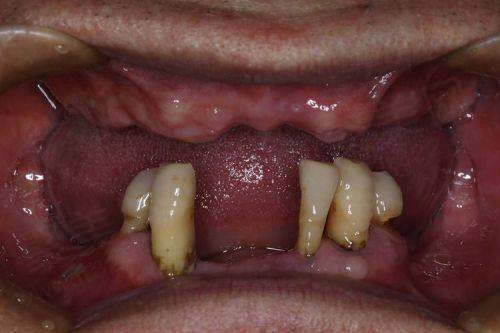

在三亚,牙齿缺失的朋友们常常会问:“三亚种植牙多少钱一颗?”这个问题可没那么简单,因为种植牙价格受到多种因素影响。2025 年,三亚种植牙市场有了新变化,单颗种植牙 2990 元起,这给不少人带来了希望。接下来,咱们就详细唠唠三亚种植牙价格的那些事儿,涵盖不同医院、不同种植体品牌的价格情况,以及影响价格的各种因素,让大家心里有个底。

2. 附加治疗需求

要是患者存在骨量不足需要植骨,或者牙龈萎缩需要软组织修复,费用可能会增加 3000 - 8000 元。这就好比盖房子,如果地基不稳,就得先加固地基,这肯定会增加成本。所以,在种植牙之前,得先检查口腔状况,看看需不需要做这些附加治疗。

在三亚,种植牙价格受到多种因素影响,2025 年单颗种植牙 2990 元起,不同品牌、不同医院的价格各有不同。大家在选择种植牙的时候,要根据自己的经济情况和医生的建议,选择适合自己的方案。同时,要警惕低价陷阱,选择正规的医疗机构和有经验的医生。牙齿缺失会影响咬合平衡和面部支撑,及时修复对维持口腔健康和面部年轻化都有重要意义。希望大家都能早日修复健康笑容,拥有一口好牙。所以,关于“三亚种植牙多少钱一颗”这个问题,相信大家现在心里都有了更清晰的答案啦。